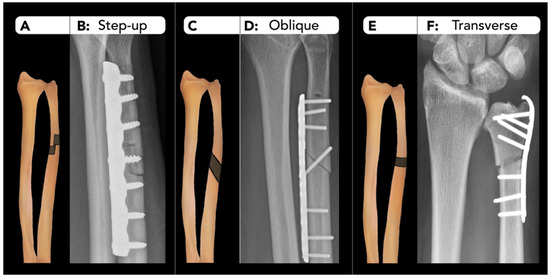

2.2.3. Distal Radius Corrective Osteotomy